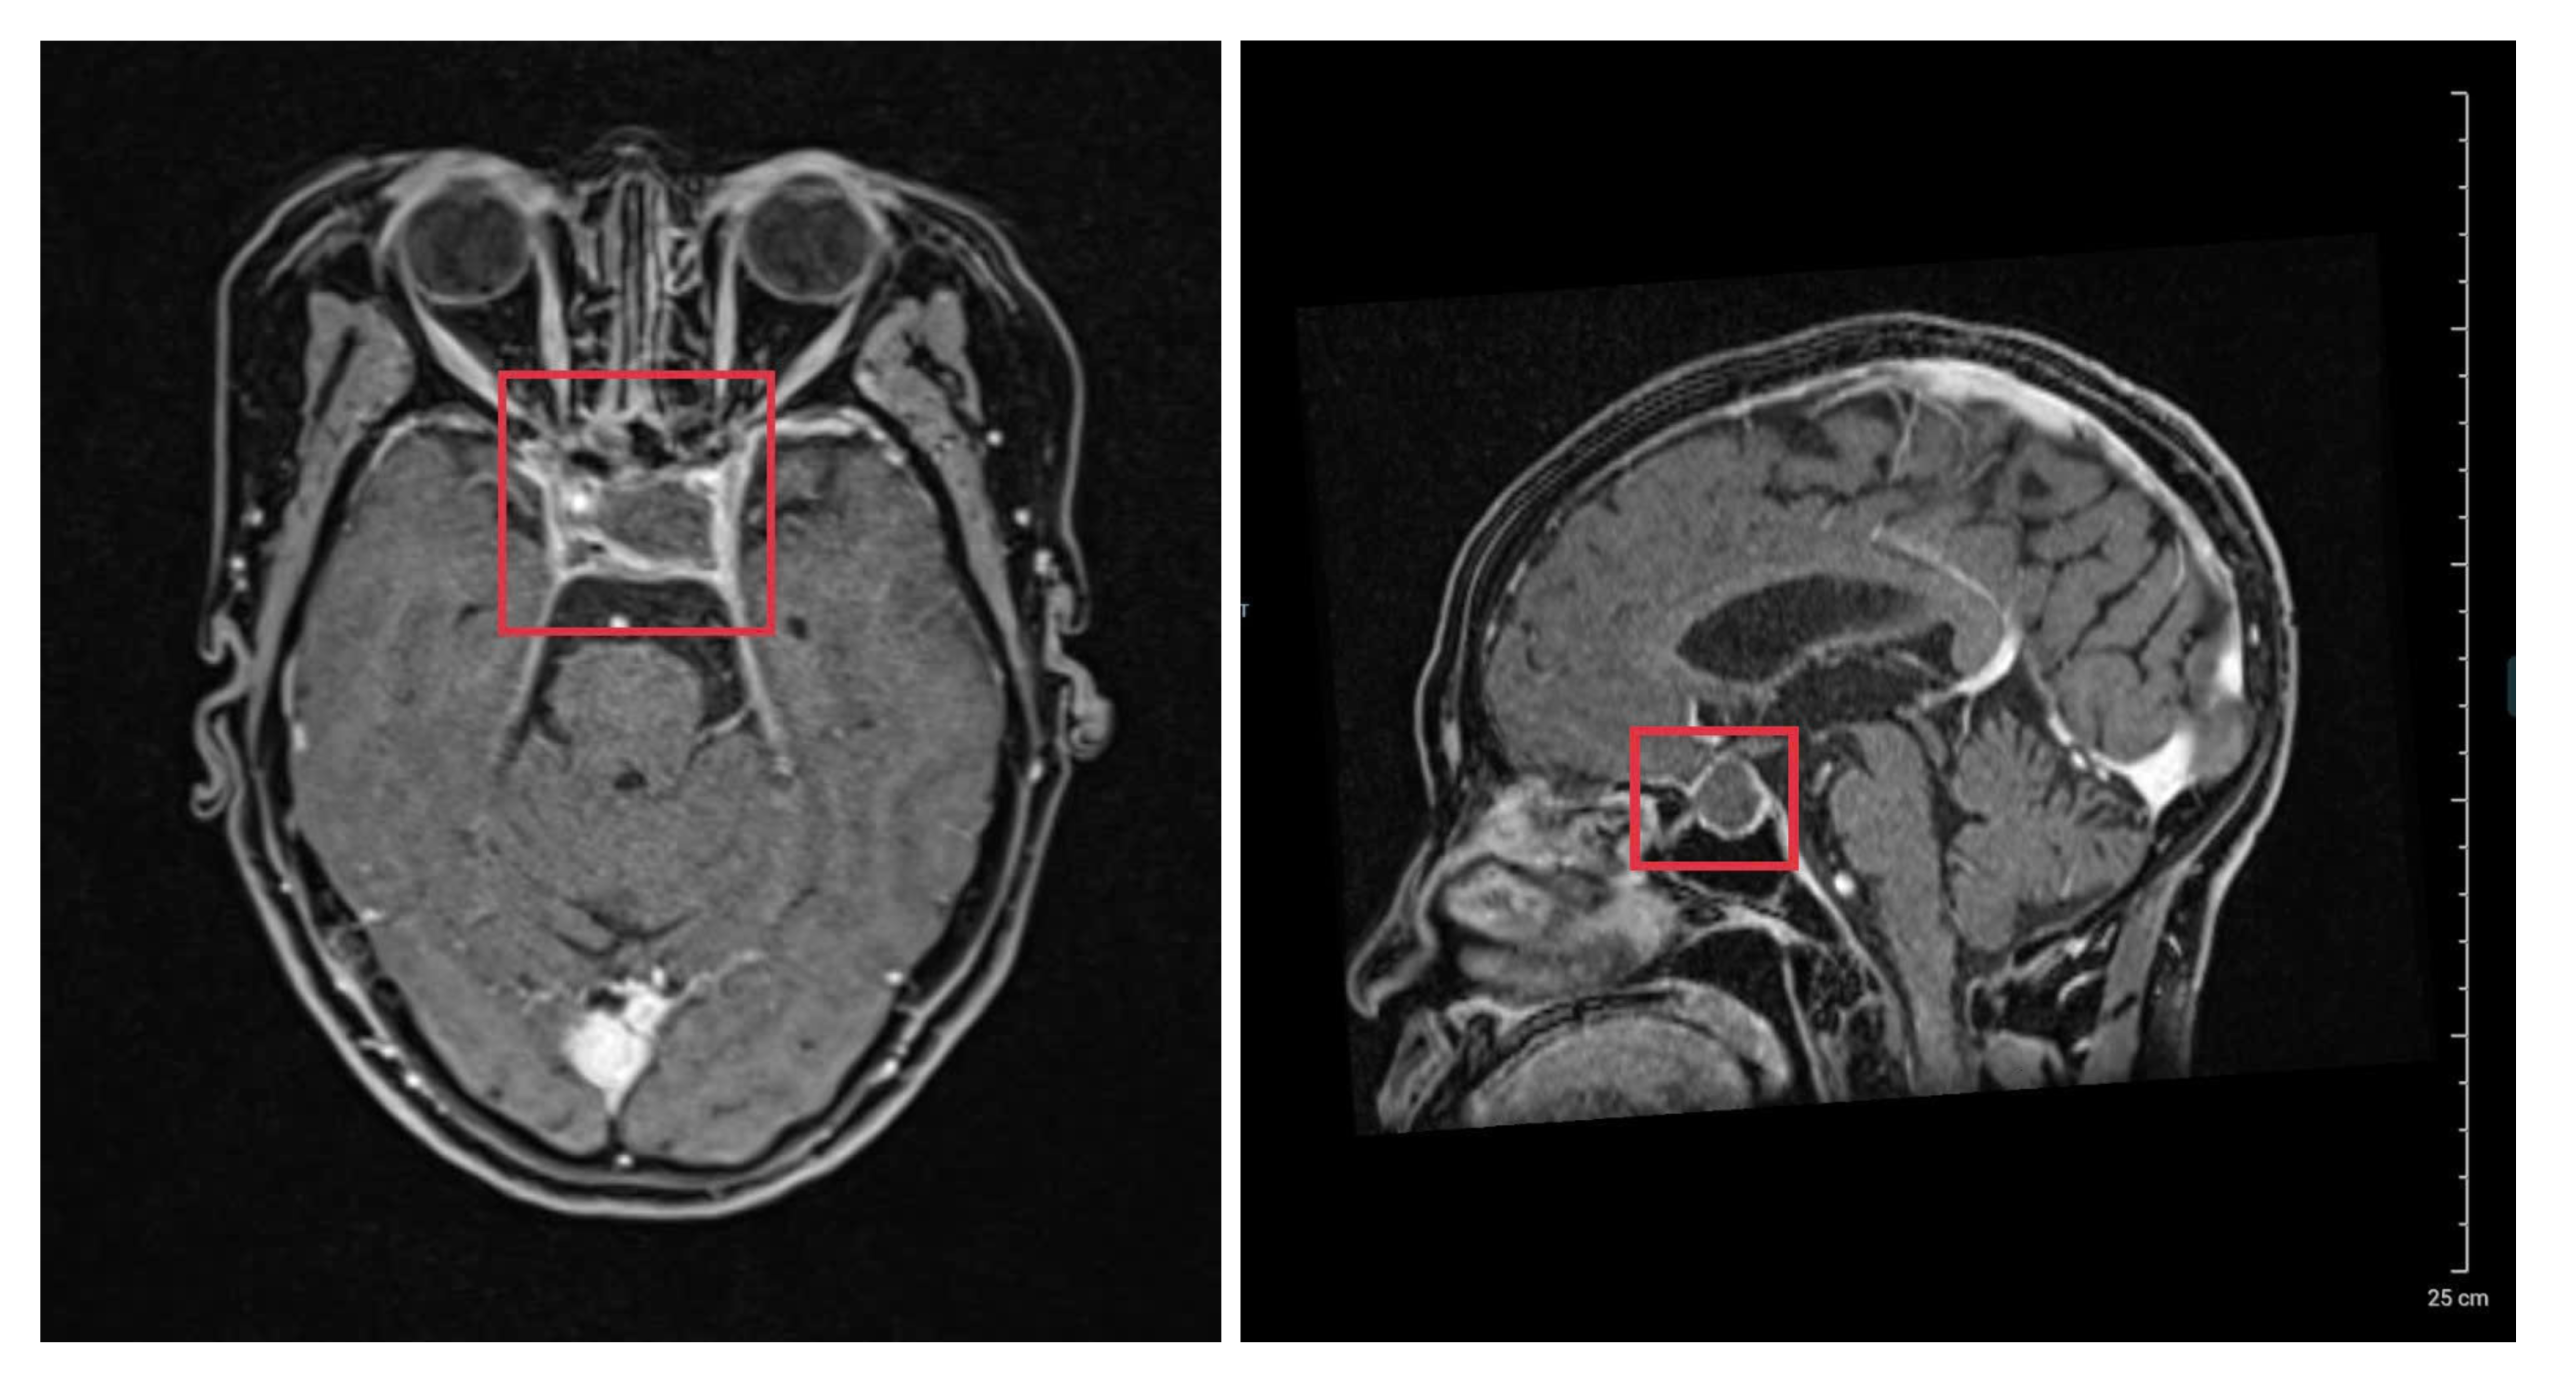

Vừa qua, khoa Phẫu thuật Thần kinh – Cột sống, BVĐK Thái Bình đã tiếp nhận bệnh nhân N.T.H (1964) trong tình trạng đau đầu, chóng mặt và suy kiệt. Kết quả chụp cộng hưởng từ (MRI) sọ não xác định bệnh nhân có khối u tuyến yên.

Các bác sĩ xác định, đây là một ca bệnh rất phức tạp do bệnh nhân có tiền sử tai biến mạch máu não tới 4 lần để lại di chứng yếu nửa người. Cùng với đó, khối u tuyến yên nằm sâu tại vùng nền sọ, bao quanh bởi mạng lưới mạch máu chằng chịt và các dây thần kinh thị giác quan trọng. Nếu không được phẫu thuật kịp thời để loại bỏ khối u, tình trạng chèn ép sẽ khiến bệnh nhân bị suy tuyến yên ngày càng nặng. Điều này không chỉ gây rối loạn nội tiết nghiêm trọng mà còn ảnh hưởng trực tiếp đến các chức năng sống, khiến sức khỏe bệnh nhân suy kiệt nhanh chóng.